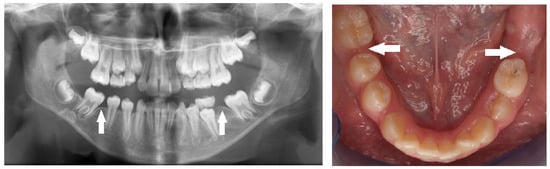

| Impaction | Failure of tooth eruption into the oral cavity. |

| Submergence | A primary tooth positioned under the occlusal surface of the adjacent teeth. |